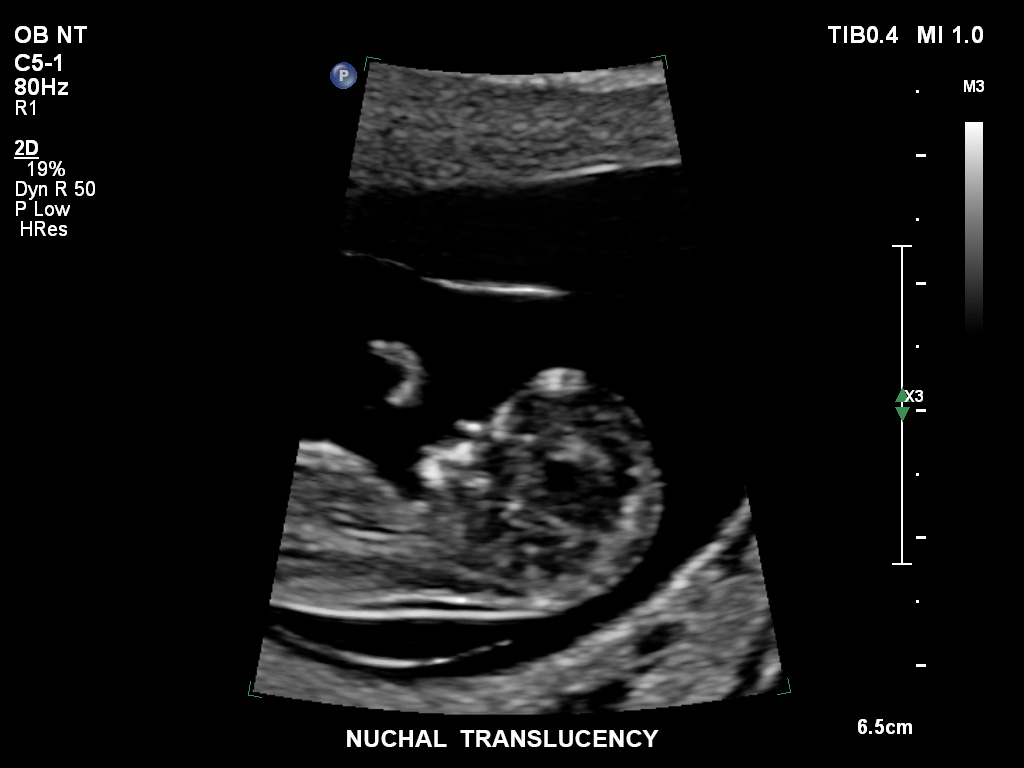

• C5-1 PureWave-Breitband-Convex-Schallkopf für hohe Eindringtiefen in der Gynäkologie und der Geburtshilfe, für Patientinnen mit Schwangerschaftsdiabetes oder vorzeitigem Blasensprung